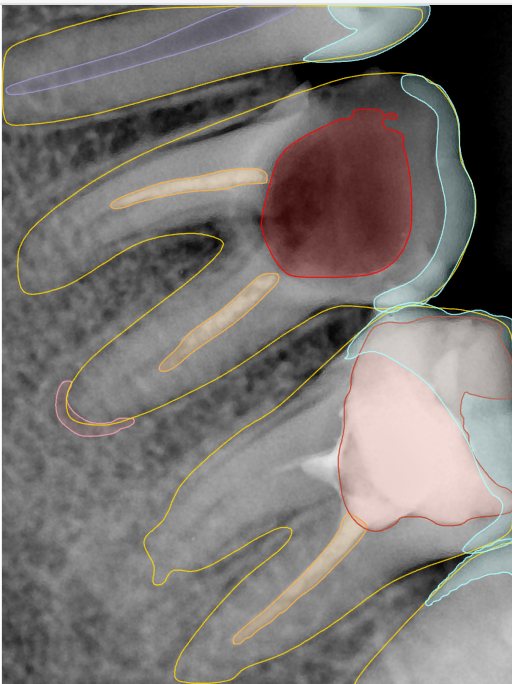

CR/DR 牙齿分割阶段记录

当前进展

- 完成了 CR/DR 牙齿相关分割训练

- 当前结果已经达到阶段预期,但仍有细节问题需要继续处理

相关测试

遇到的问题

- 训练过程中出现过 mask 下移问题

- 部分结果会出现 box 填充异常

- mask 边缘仍然有比较明显的锯齿感

第二版算法问题测试

Updated: 2026-04-13(更新日期)

| 第一版 | 第二版 | 是否解决 | |